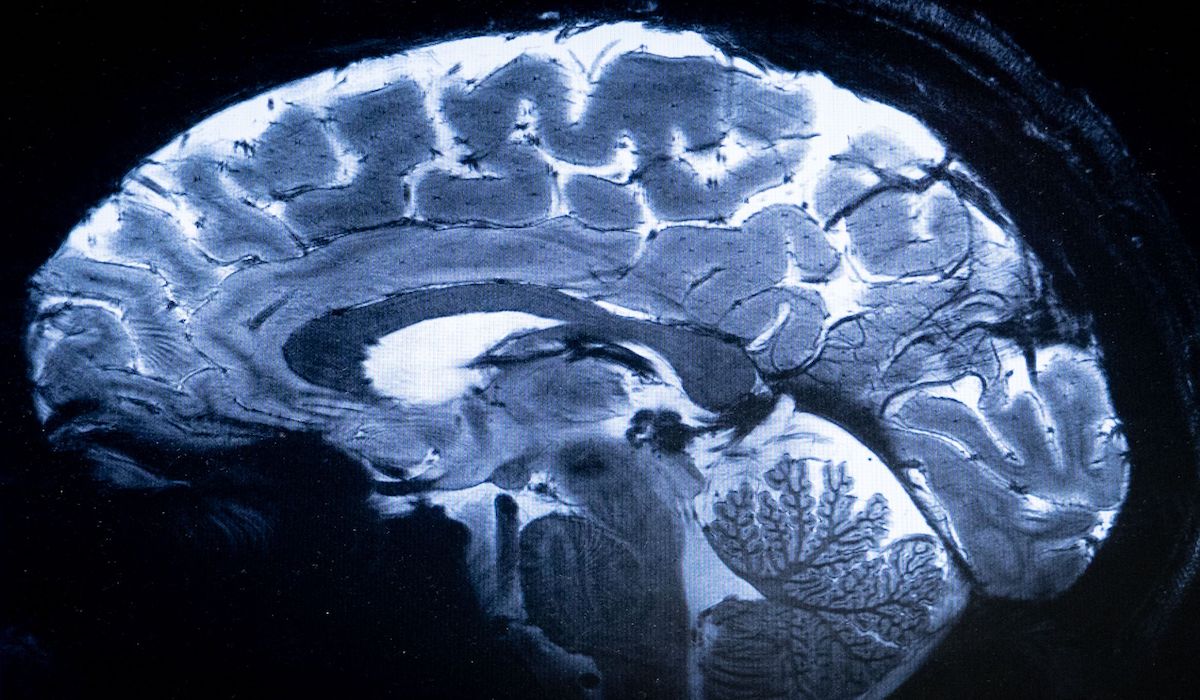

Magnetic Resonance Imaging (MRI) sudah lama menjadi standar emas di dunia medis modern.

Magnetic Resonance Imaging atau yang biasa disebut MRI, memungkinkan peneliti untuk melihat detail otak manusia dengan tingkat presesi baru.